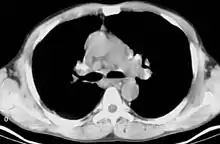

CT scan of the chest showing bilateral lymphadenopathy in the mediastinum due to sarcoidosis.

Bilateral hilar lymphadenopathy is a bilateral enlargement of the lymph nodes of pulmonary hila. It is a radiographic term for the enlargement of mediastinal lymph nodes and is most commonly identified by a chest x-ray.